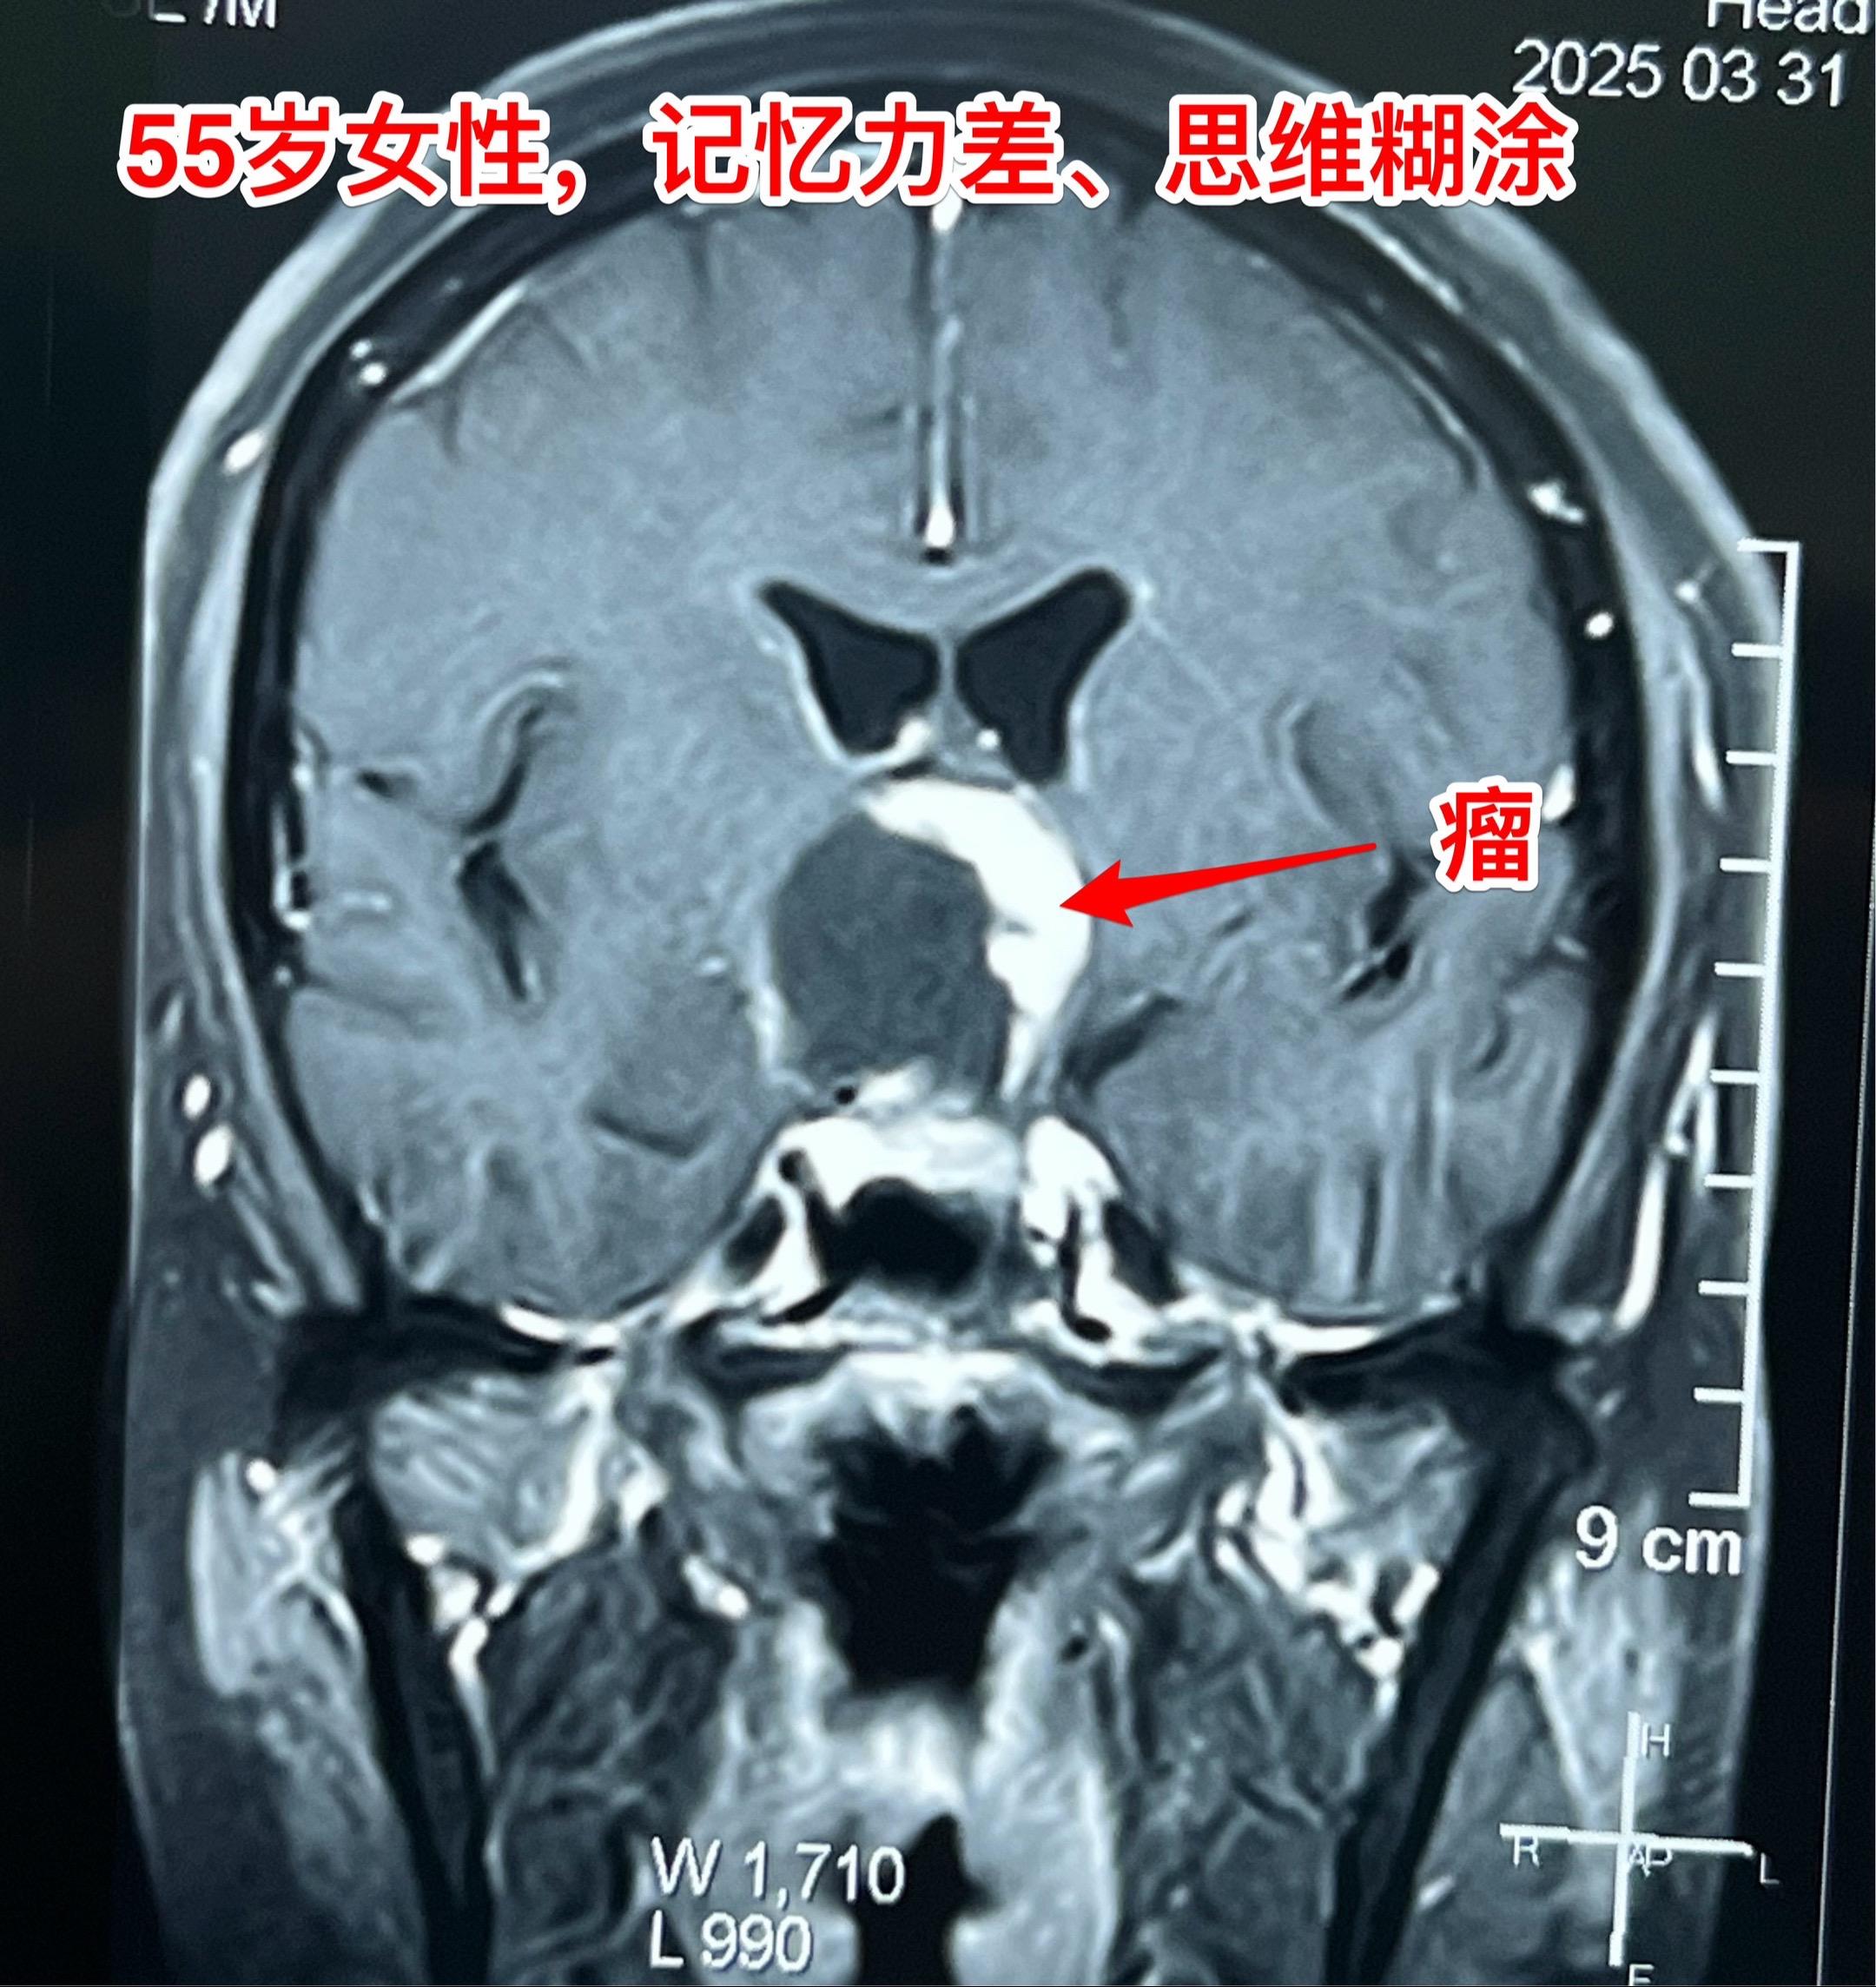

第一眼就诊断为颅咽管瘤,病理报告却不是。55岁女性因记忆力下降,有时思维糊涂就医,行脑部磁共振和CT检查发现鞍上区域囊性肿瘤,伴有钙化。 鞍上的囊性肿瘤伴有钙化,病人年龄55岁,第一印象就是颅咽管瘤。这是常规思维。 手术中发现肿瘤边界不清楚,肿瘤的钙化也不是颅咽管瘤那样的白色钙化,送了两次快速冰冻病理检查,报告提示是胶质瘤。 临床上看病首先考虑的是常见病,读书的时候老师就是这样教的。 事实上,临床上常见病能见到,罕见病也能见到。通常情况下下丘脑胶质瘤是